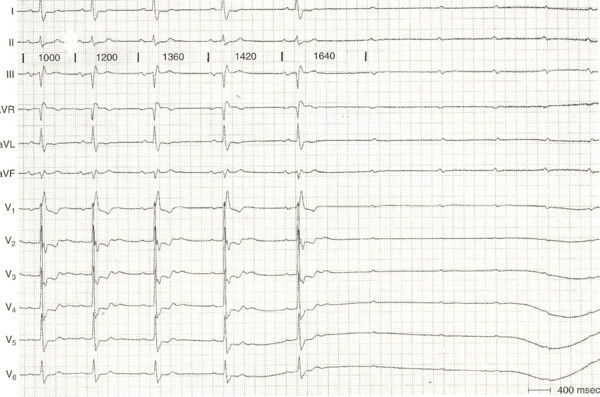

Phase 4 Block, Figure 1

- Phase 4 block in the His-Purkinje system occurring after an atrial premature beat that conducts to the ventricles. Notice the delayed sinus beat that results in a critical P-P lengthening with subsequent Phase 4 block in the His.